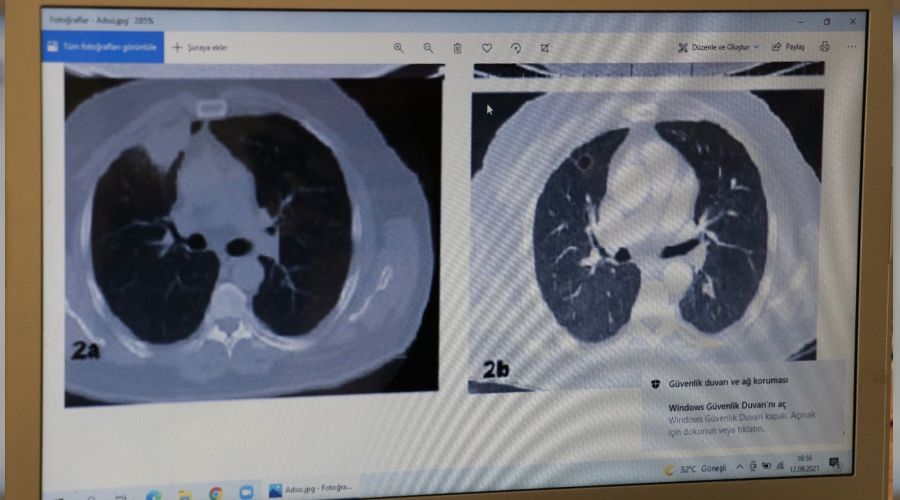

Kahramanmaraş dışında çalışan 52 yaşındaki N.T., göğüs ağrısı şikayetiyle gittiği hastanede sağ akciğerinde 4 santimetre çapında tümör tespit edildi. Kanser olabileceği şüphesiyle yapılan tetkikler sonrası N.T.'ye akciğer kanseri teşhisi konularak ameliyat yapılmasına karar verildi. Ameliyatı Kahramanmaraş'ta olacağını söyleyen hasta Sütçü İmam Üniversitesi Sağlık Uygulama ve Araştırma Hastanesi Göğüs Cerrahisine başvurdu. Burada Anabilim Dalı Öğretim Üyesi Dr. Fatoş Kozanlı tarafından yapılan tetkikler sonrası ameliyata girmesi söylendi. Ameliyat öncesi her hastadan alınan korona testi pozitif çıkan hasta endişe oluştururken, tedavisine başlanan N.T.'nin son testi negatif çıktı.

Dr. Fatoş Kozanlı, tedavi sonrası tomografisi çekilen N.T.'nin akciğerindeki tümörün yok olduğunu belirlerken, 'Hastanın sağ akciğerinde 4 santimetreye ulaşan bir lezyon tespit edildi. Sonra akciğer tomografisi çekiliyor ve yine sağ akciğer 4 santimetre büyüklüğünde radyolojik özelliği olarak akciğer kanserine benzeyen lezyonlar görülüyor' dedi. Hastanın başka şikayetinin olmadığını söyleyen Dr. Kozanlı, 'Ön planda akciğer kanseri düşünülerek akciğer kanserini ekarte etmek için yapılan bir çalışma yapıyoruz. Bir operasyona planladık. Sağlık Bakanlığımızın kuralları gereği ameliyata alacağımı her hastaya Covid-19 testi yapılıyor ve biz de PCR testi yaptık.

Hastaya antiviral tedavi verdik ve evine geldik. 14 gün sonra yeniden başvurması ve negatife dönünce ameliyatı yapacaklarını söyledik. Hasta tedavisini oldu 14 gün sonra geldi ve artık negatifleşmişti. Ameliyata hazırladık. Ve son kez bir akciğer tomografisi çektik ve lezyonun tamamen ortadan kalktığını gördük. Eğer akciğer kanseri olmuş olsaydı tümör bu şekilde ortadan kalkmazdı. Daha kendi çalışmalarımızı inceledik, Türkiye ve dünyadaki çalışmaları inceledik. Dünya literatürünü yeniden gözden geçirdik ve benzer bulgulara rastlamadık' dedi.İHA

Dr. Fatoş Kozanlı, tedavi sonrası tomografisi çekilen N.T.'nin akciğerindeki tümörün yok olduğunu belirlerken, 'Hastanın sağ akciğerinde 4 santimetreye ulaşan bir lezyon tespit edildi. Sonra akciğer tomografisi çekiliyor ve yine sağ akciğer 4 santimetre büyüklüğünde radyolojik özelliği olarak akciğer kanserine benzeyen lezyonlar görülüyor' dedi. Hastanın başka şikayetinin olmadığını söyleyen Dr. Kozanlı, 'Ön planda akciğer kanseri düşünülerek akciğer kanserini ekarte etmek için yapılan bir çalışma yapıyoruz. Bir operasyona planladık. Sağlık Bakanlığımızın kuralları gereği ameliyata alacağımı her hastaya Covid-19 testi yapılıyor ve biz de PCR testi yaptık.

Hastaya antiviral tedavi verdik ve evine geldik. 14 gün sonra yeniden başvurması ve negatife dönünce ameliyatı yapacaklarını söyledik. Hasta tedavisini oldu 14 gün sonra geldi ve artık negatifleşmişti. Ameliyata hazırladık. Ve son kez bir akciğer tomografisi çektik ve lezyonun tamamen ortadan kalktığını gördük. Eğer akciğer kanseri olmuş olsaydı tümör bu şekilde ortadan kalkmazdı. Daha kendi çalışmalarımızı inceledik, Türkiye ve dünyadaki çalışmaları inceledik. Dünya literatürünü yeniden gözden geçirdik ve benzer bulgulara rastlamadık' dedi.İHA